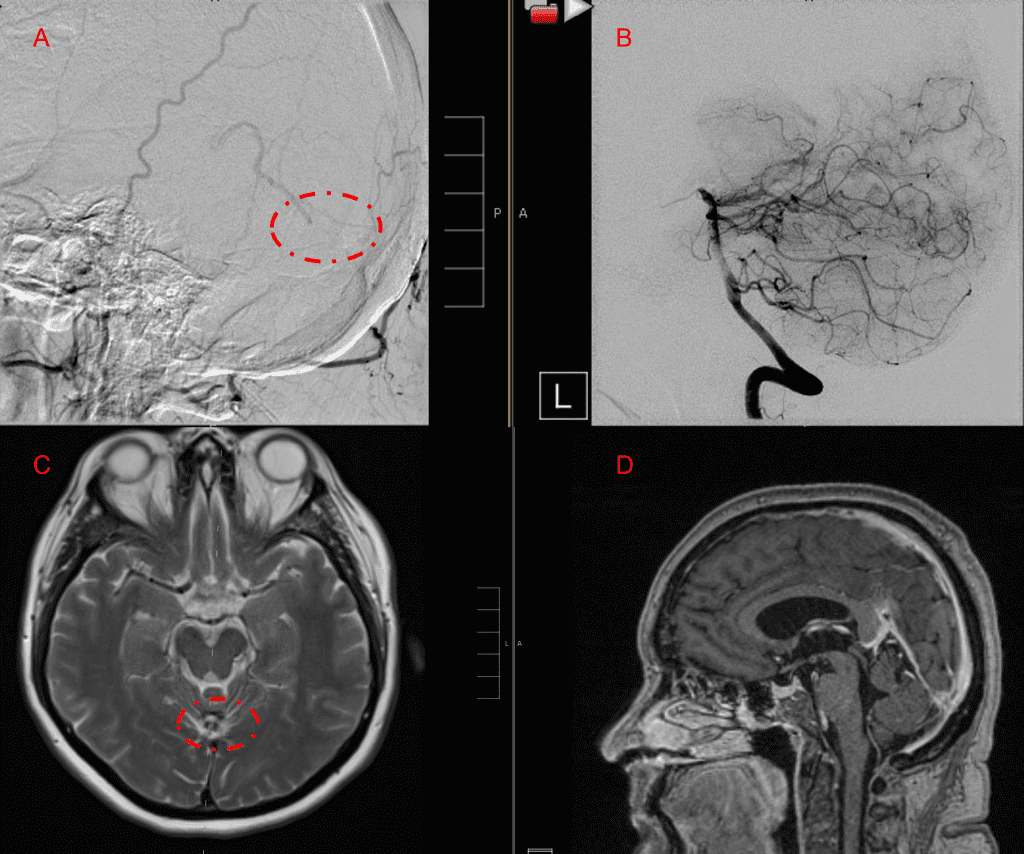

Figure 6. MRI and Catheter Angiograms precisely localize the residual A-V shunts vessels to perform Gamma-Knife Radiosurgery to deliver therapeutic doses to the targets.